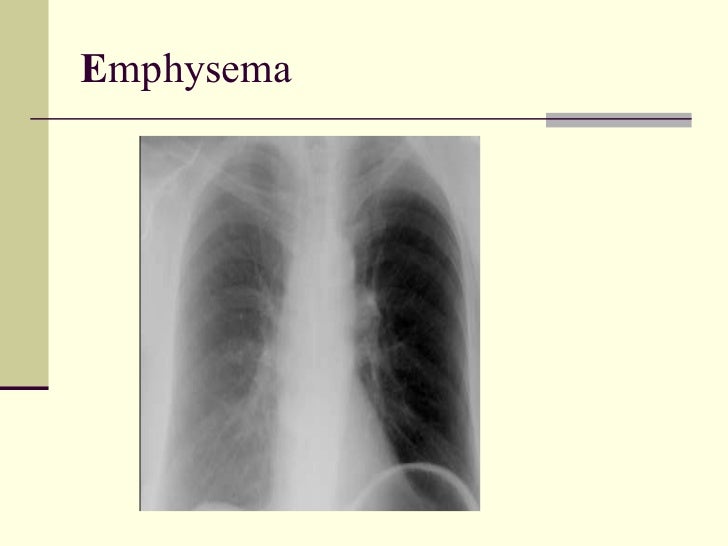

37. 38. EMPHYSEMA <ul><li>Alpha 1 Anti-Trypsin Deficiency </li></ul><ul><li>Hyperinflation </li></ul><ul><li>Hyperlucency </li></ul><ul><li>Low set flat diaphragm </li></ul><ul><li>Vertical heart </li></ul><ul><li>Pre and infra cardiac lungs </li></ul><ul><li>Barrel shape </li></ul><ul><li>Emphysema </li></ul><ul><li>Avascular zones </li></ul><ul><li>Cephalization of upper lung fields is not evident </li></ul><ul><li>Predominant basal involvement (not evident) </li></ul>

43. 48. E mphysema